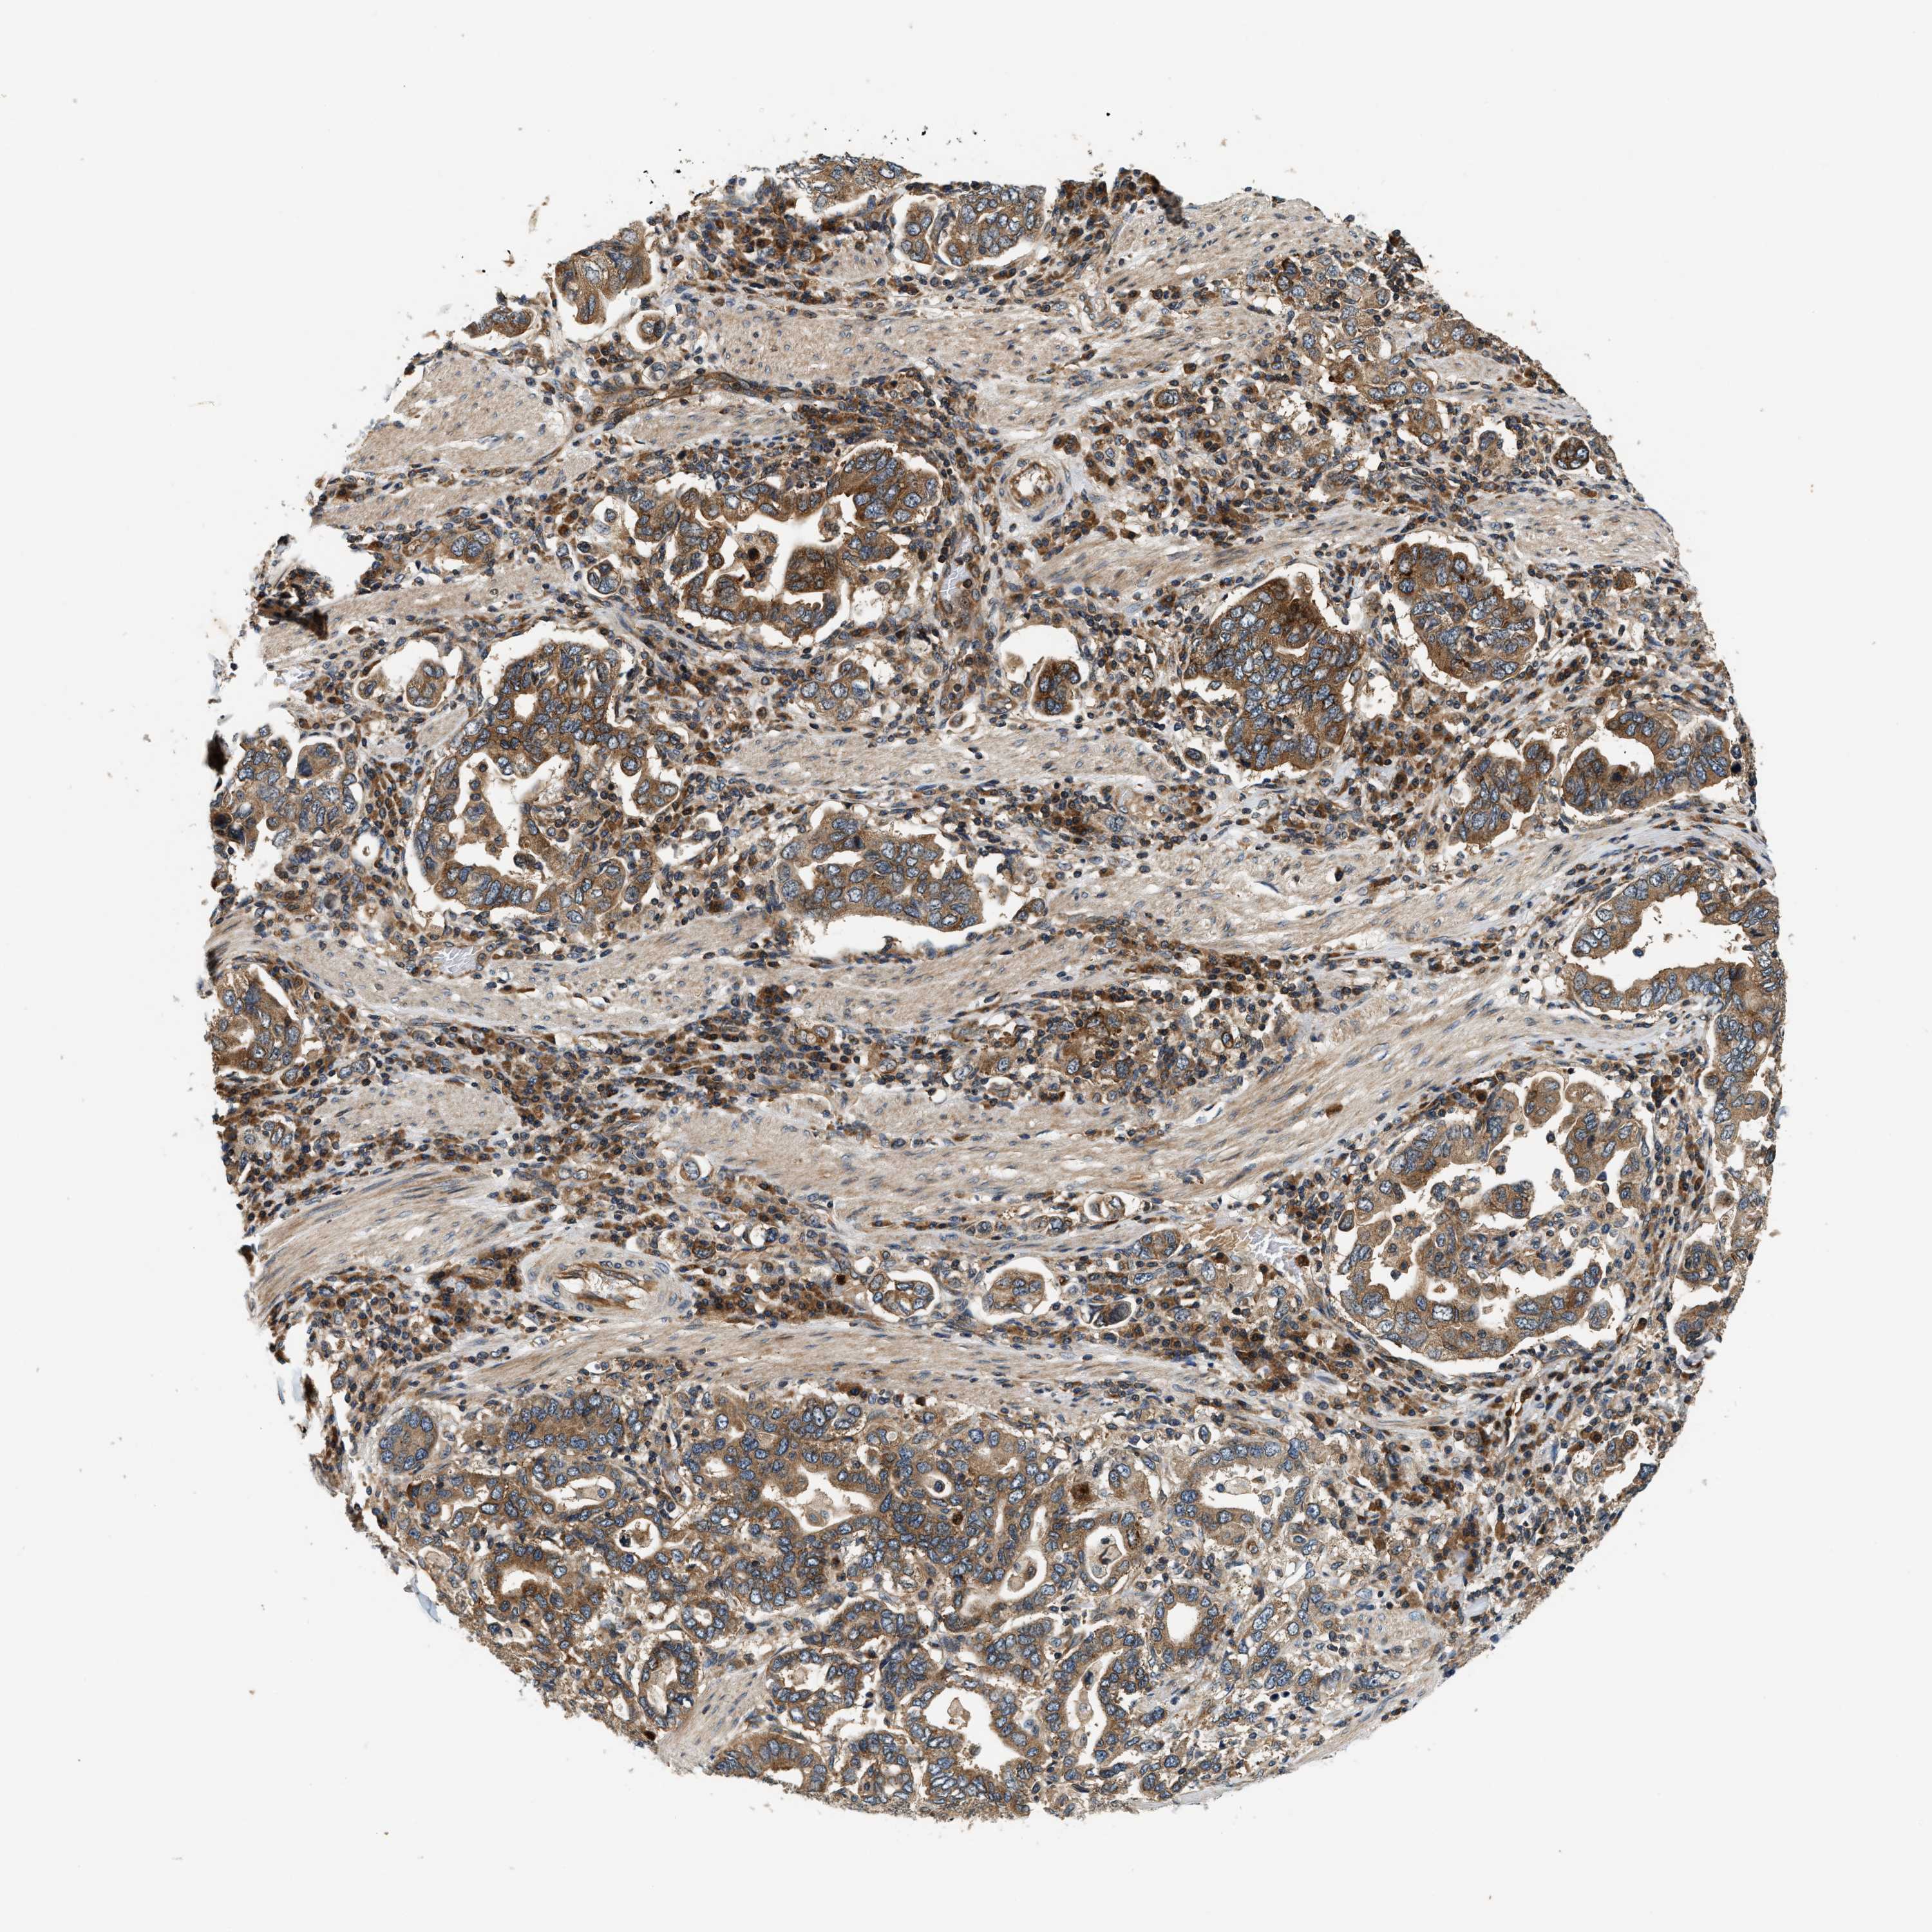

STOMACH CANCER - Protein expressioni

A mouse-over function shows sample information and annotation data. Click on an image to view it in a full screen mode. Samples can be filtered based on level of antibody staining by selecting one or several of the following categories: high, medium, low and not detected. The assay and annotation is described here.

Note that samples used for immunohistochemistry by the Human Protein Atlas do not correspond to samples in the TCGA dataset.

Antibody stainingi

Antibody staining in the annotated cell types in the current human tissue is reported as not detected, low, medium, or high, based on conventional immunohistochemistry profiling in selected tissues. This score is based on the combination of the staining intensity and fraction of stained cells.

Each image is clickable and will lead to virtual microscopy that enables deeper exploration of all samples and also displays staining intensity scores, fraction scores and subcellular localization as well as patient and tissue information for each sample.

Antibody HPA021318

Antibody HPA021319

Staining

High

Medium

Low

Not detected

Intensity

Strong

Moderate

Weak

Negative

Quantity

>75%

75%-25%

<25%

None

Location

Nuclear

Cytoplasmic/membranous

Cytoplasmic/membranous,nuclear

Adenocarcinoma, NOS